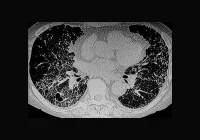

Patients presenting with atypical chest pain often undergo invasive coronary angiography (ICA) to diagnose or exclude coronary artery disease (CAD). Although effective, ICA is costly and involves procedural risks. An alternative approach using coronary computed tomography (CT) offers a less invasive and potentially more efficient diagnostic pathway. A recent randomised controlled trial provides compelling evidence that CT not only delivers equivalent clinical outcomes to ICA but does so at a significantly lower cost. This suggests that a CT-first strategy could serve as a more economically sustainable standard for managing atypical chest pain.

The CAD-Man trial enrolled 329 patients who were clinically referred for ICA due to suspected CAD. These individuals exhibited atypical chest pain, defined by the presence of one or two of the classical features of angina. Patients were randomly assigned to either receive CT or proceed directly to ICA. The primary aim was to evaluate cost-utility by measuring quality-adjusted life years (QALYs) and overall healthcare costs over a three-year period.

The results showed no significant difference in QALYs between the CT and ICA groups at any follow-up point. At three years, patients in the CT group achieved an average of 2.09 QALYs compared to 2.11 in the ICA group. Despite this clinical equivalence, CT proved substantially more economical. Total costs per patient were €1543 lower for those in the CT group. These savings emerged largely from reduced initial management costs and lower utilisation of inpatient services. CT can typically be conducted on an outpatient basis, avoiding the hospital stay that ICA often requires. Furthermore, CT led to fewer subsequent procedures, including revascularisations and repeat angiographies, which further reduced overall costs.